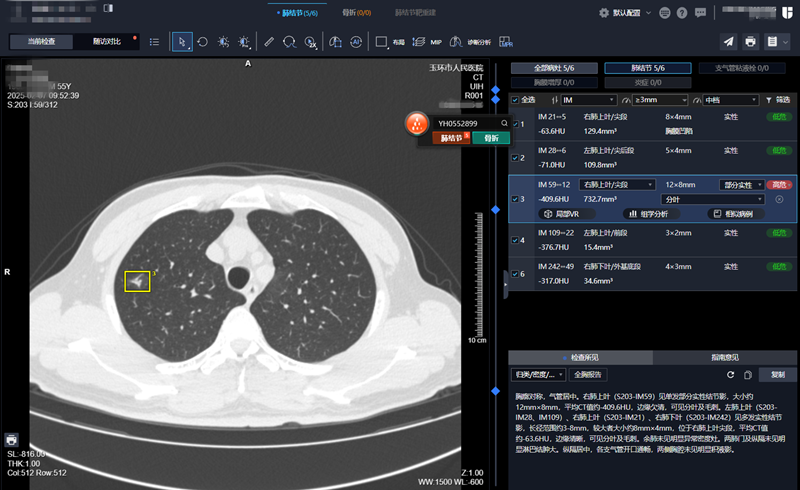

55岁的张先生在玉环市人民医院进行胸部CT检查时,机器扫描后的数据迅速传输至PACS系统。AI辅助诊断系统仅用时1分钟左右便处理完海量数据,并自动生成了详细报告。

报告中不仅列出了张先生体内的5个肺结节的具体位置、大小、密度和形态等各种信息,还特别用红色标记了一个高风险病灶。张先生后续也在玉环市人民医院进行手术治疗,病理结果证实了AI的诊断是准确的,该高风险病灶确为早期肺癌。

放射科副主任医师苏维杰表示:“通常,人工阅读一份胸部CT需要5-10分钟,而AI的平均检测时间仅为1-2分钟。我们基于AI的初步诊断结果进行人工复核,大大提高了报告的准确性和工作效率。”

放射科主任赵顺标补充道:“AI技术早在2018年就在我院放射科得到广泛的应用,包括肺结节、心脑头颈血管、脑灌注、肋骨骨折、乳腺等疾病的诊断,尤其在肺结节检测方面,AI能快速识别直径小于5mm的微小磨玻璃结节,将直径小于3mm结节检出率提高30%左右。”